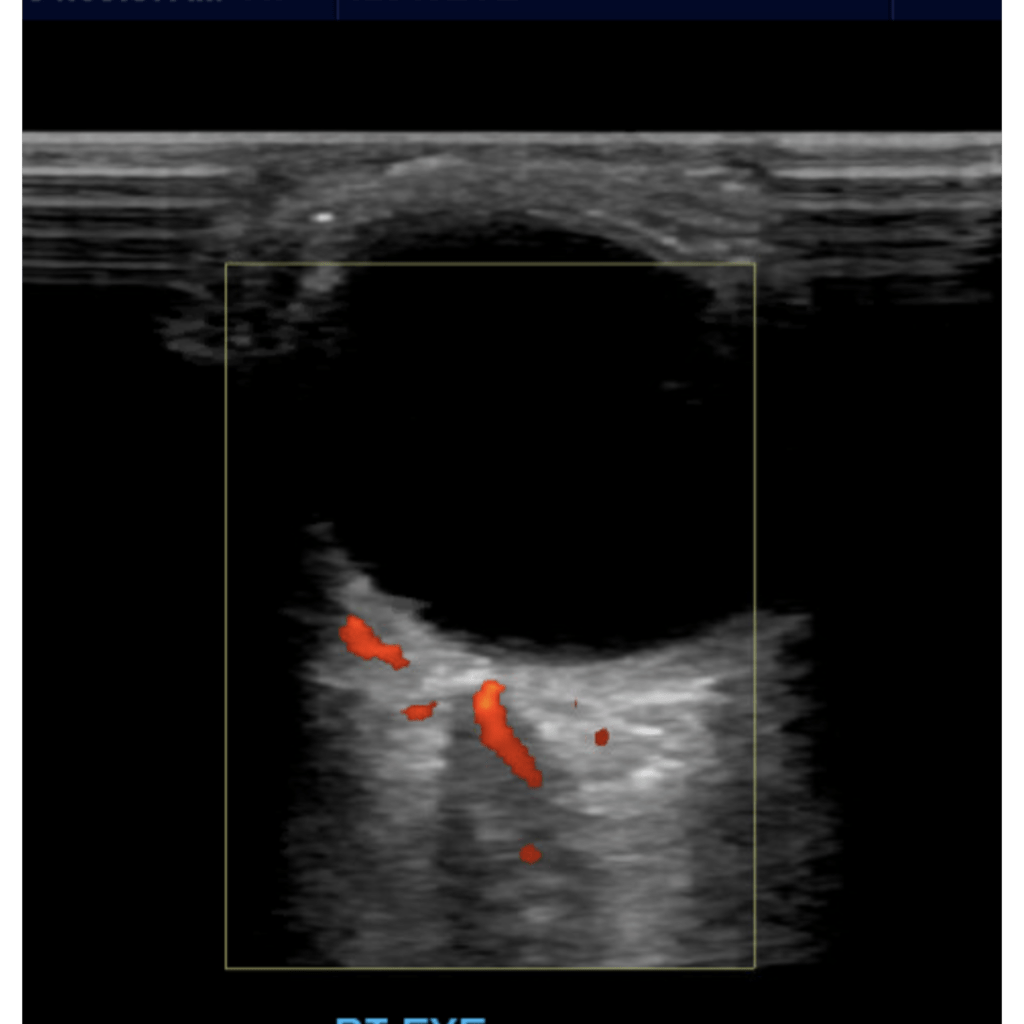

Central Retinal Artery Occlusion

Blockage of the central retinal artery usually due to an atherosclerotic thrombus (typically from an internal carotid artery plaque). Presents with sudden, painless, partial or complete monocular loss of vision. Also associated with giant cell arteritis. Patient describes “shade” or “curtain” coming down over entire visual field in the affected eye. Bilateral presentation is rare.

Sonographically you’ll encounter an echogenic foci posterior to the optic disc “bright dot sign” with lack of color or spectral flow distal to the thrombus